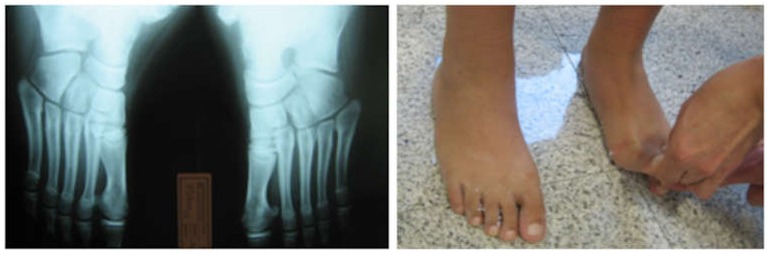

Eικόνα 1(β): Πλατυποδία

Εικόνα Η κλινική εικόνα δύσκαμπτης πλατυποδίας, με αδυναμία σχηματισμού ποδικής καμάρας στην στήριξη στις μύτες και ακτινολογική εικόνα με κάθετο αστράγαλο.

Είναι χαρακτηριστική η δυσχέρεια σχηματισμού ποδικής καμάρας στην στήριξη στις μύτες των ποδιών και σε ανύψωση στο μεγάλο δάκτυλο.

Εικόνα Συνοστέωση πτέρνας  σκαφοειδούς αριστερά, με δυσχέρεια δημιουργίας της ποδικής καμάρας στην ανύψωση του μεγάλου δακτύλου.